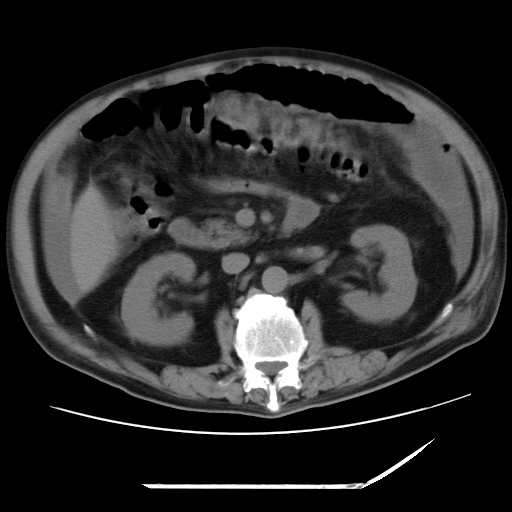

以下是引用zxl51642在2009-8-12 18:55:00的发言:[br]1、肠系膜脂肪浑浊,密度增高,腹水,支持腹膜炎诊断;2、右肾盂及输尿管中段结石,左输尿管起始段结石;3、胆囊切除术后改变?4、双侧胸膜腔少量积液;5、胰腺体积不大,勾勒清楚,肾前筋膜无增厚,不支持胰腺炎,请结合血尿淀粉酶及临床。